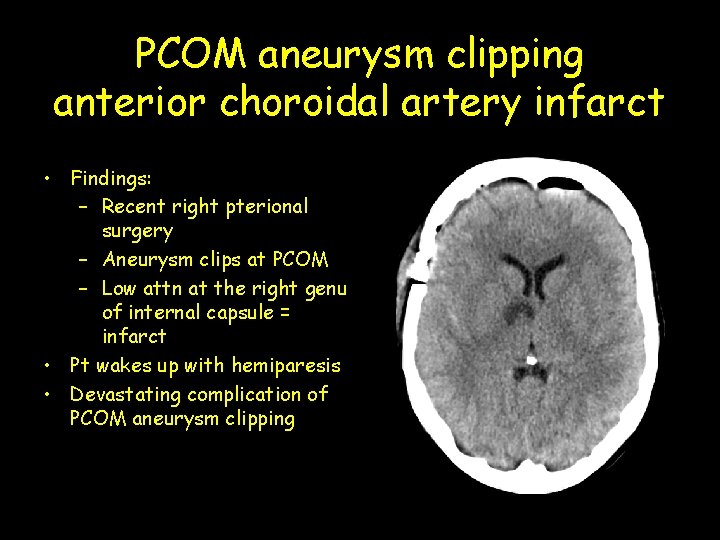

PCOM aneurysm clipping anterior choroidal artery infarct • Findings: – Recent right pterional surgery – Aneurysm clips at PCOM – Low attn at the right genu of internal capsule = infarct • Pt wakes up with hemiparesis • Devastating complication of PCOM aneurysm clipping